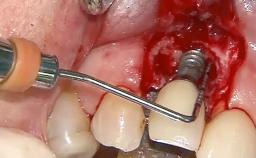

Due to their promising clinical performance, zirconia implants have recently become popular alternatives to titanium implants, particularly for areas with high esthetic demands (Holländer and coworkers 2016; Roehling and coworkers 2016; Lorenz and coworkers 2019). However, regardless of the reported high survival and success rates, zirconia implants were affected by peri-implant diseases over the short observation period, suggesting the importance of treating peri-implant diseases at zirconia implants (Becker and coworkers 2017). In their case, Frank Schwarz and Ausra Ramanauskaite present 3-year results following mechanical debridement alongside Er:YAG laser monotherapy.